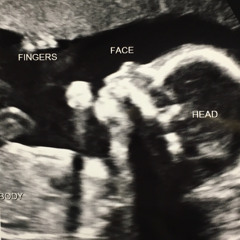

my daughter added some vocals on this one, who would think this song would be about kitties?